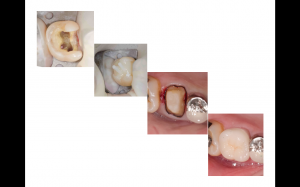

先日も金属の詰め物に隙間が出てきたので外してみると虫歯に、、、

神経までは達していなかったので、虫歯を取り除いて詰め物を作っていくことになりました。

患者さんは白い歯を希望され、奥歯で強い力がかかる部位でもあったのでセラミックを希望されました。

色や咬み合わせも問題なく、できるだけ長持ちするように定期検診していきたいですね。